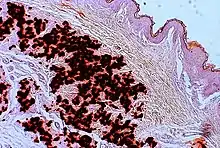

- Diagnostic histopathological changes in lesional skin: Calcified elastic fibers in the mid and lower dermis, confirmed by positive calcium stain

| Pseudoxanthoma elasticum | LM: Mid-dermal calcification and fragmentation of elastic fibers EM: Mineralization in elastic fiber core |

| PXE-like papillary dermal elastolysis | LM: Selective elastic tissue elimination in the papillary dermis and presence of melanophages |